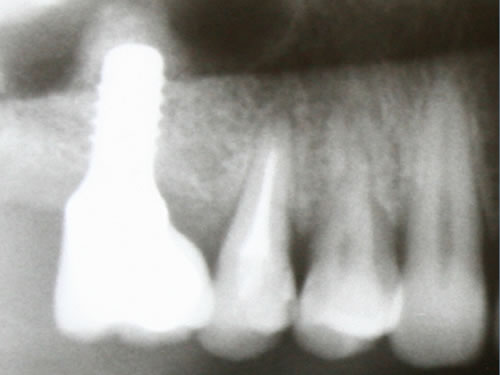

Die Backenzähne sind häufig die ersten Zähne, die entfernt und ersetzt werden müssen. Wenn alle Backenzähne einer Kieferhälfte fehlen, spricht man von einer verkürzten Zahnreihe oder einer Freiendsituation. Hier fehlt der für eine Brücke notwendige hintere Pfeiler (Abb. 3.19 bis 3.21).

Abb. 3.19: Röntgenbild einer beidseitigen Freiendsituation im Unterkiefer und einer Schaltlücke im Oberkiefer.

Abb. 3.20: Freiendsituation mit zwei eingesetzten Implantaten.

Abb. 3.21: Eingliederung einer verschraubten Brücke mit einem Drehmomentschlüssel.

Mit Hilfe künstlicher Zahnwurzeln kann bei derartig verkürzten Zahnreihen im Unterkiefer eine Brücke ­angefertigt werden. Damit lassen sich das "Herunterwachsen" oder "Heraufwachsen" (Elongation) der Gegenzähne so wie das Kippen verhindern und die Kaufunktion mit einem festsitzenden Zahnersatz wiederherstellen.